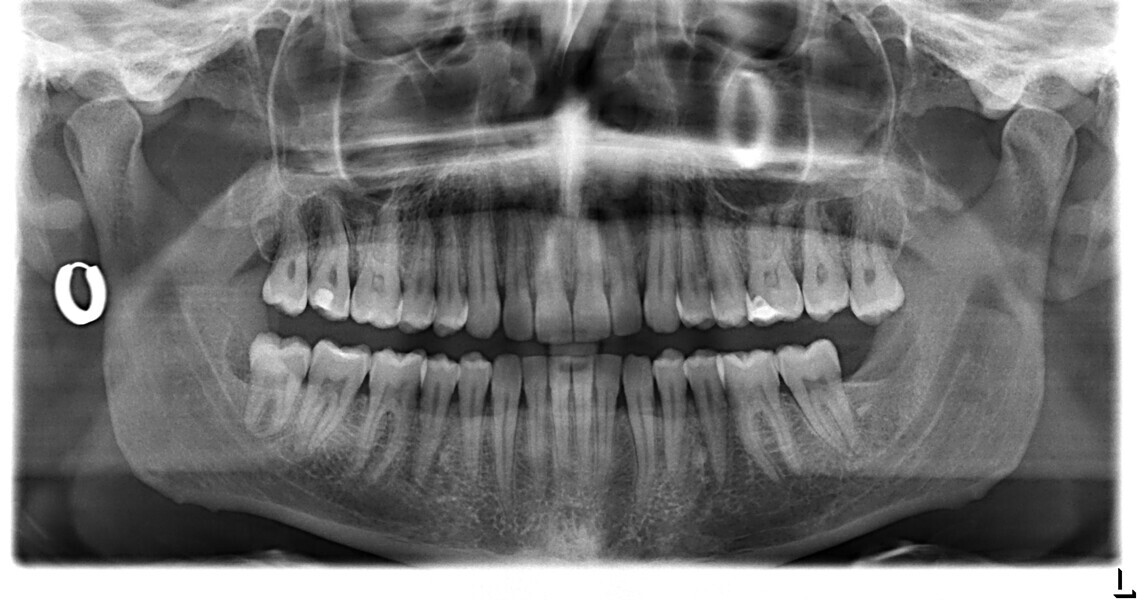

Le motif principal de consultation de ce patient âgé de 37 ans, était de rétablir l’alignement des dents antérieures sur les deux arcades. L’analyse faciale a indiqué une face courte avec un profil plat, mais une projection normale du menton (Figs. 9–12), et l’examen clinique a révélé une classe squelettique de type I (angle ANB = 0,89°) et une malocclusion de classe I avec supraclusion sévère (près de 100 %), une courbe de Spee très prononcée, un torque normal de l’incisive centrale supérieure (Ui-FH = 110°), un encombrement dentaire léger sur l’arcade maxillaire et modéré sur l’arcade mandibulaire (Figs. 13–18). Chez ce patient, les composantes de la supraclusion correspondaient à une dysmorphie squelettique grave correspondant à une hypodivergence (FMA = 14,24°), avec une inclinaison normale des incisives supérieures et inférieures et un angle goniaque réduit (110,46°). L’analyse du cliché céphalométrique indiquait une hauteur réduite de l’étage inférieur de la face associée à l’hypodivergence (Fig. 19). La seule option de traitement envisagée était un traitement orthodontique par aligneurs avec tous les éléments auxiliaires décrits (rampes d’occlusion, zones de pression, nivellement de la courbe de Spee dans les trois dimensions, élastiques de classe II et puissants contacts occlusaux) afin de corriger la supraclusion.

Le plan de traitement numérique (ClinCheck) avait prévu douze aligneurs pour l’arcade maxillaire et dix-sept pour l’arcade mandibulaire. Les objectifs du traitement visaient à combiner les mouvements verticaux d’extrusion des dents postérieures et les mouvements d’intrusion des dents antérieurs, au moyen de rampes d’occlusion, tout en utilisant des taquets d’extrusion pour assurer la désocclusion des dents postérieures et l’intrusion des dents antérieures inférieures, nécessaires au nivellement de l’arcade mandibulaire. La courbe de Spee a été nivelée et le profil plat ainsi que la position des lèvres ont été améliorés par une vestibulo-version des incisives supérieures et inférieures. Le plan avait prévu des élastiques de classe II pour faciliter la vestibulo-version des dents inférieures et les puissants contacts occlusaux postérieurs, avec une extrusion relative des dents postérieures. Une morphologie plus large de l’arcade et une intercuspidation idéale ont été obtenues par des mouvements de torque proches de 0° des dents latérales et postérieures supérieures. Aucune conception technique excessive n’avait été prévue dans le plan de traitement numérique. En raison de l’âge du patient, les aligneurs ont été changés tous les dix jours, dans le cadre d’un traitement d’une durée inférieure à six mois. À la fin de la première série d’aligneurs (Figs. 20–24), un nouveau plan de traitement numérique comportant cinq autres aligneurs a été conçu, en vue d’améliorer l’intercuspidation des molaires sans élastiques. La durée totale du traitement a donc été prolongée jusqu’à 7,5 mois puisque les aligneurs supplémentaires étaient changés toutes les semaines.

À la fin du traitement, on pouvait observer une relation de classe I des canines et des molaires, une légère augmentation de l’inclinaison des incisives supérieures (Ui-FH = 112°), une correction complète de l’inclinaison des incisives inférieures (IMPA = 97,09°) grâce à la vestibulo-version, et une légère amélioration de l’hypodivergence (SN-GoGn = 27°) résultant de l’extrusion relative des dents postérieures, et de l’utilisation d’élastiques de classe II — petite variation (1°) très intéressante compte tenu de l’âge du patient (Figs. 25–35). La ligne du sourire était harmonieuse et correspondait à une relation idéale entre les incisives supérieures et la lèvre inférieure. Le sourire avait été élargi grâce au contrôle du torque des segments latéraux et postérieurs.

Les relations squelettiques verticales semblent en outre être influencées par l’utilisation des éléments auxiliaires des aligneurs, puisque les repères céphalométriques verticaux indiquent un changement positif. Chez ce patient, ni intrusion des dents postérieures ni effet de mordu n’ont été constatés à la fin ou au cours du traitement. La modification globale de la position verticale des dents postérieures était minime, mais comme il a été mentionné, la littérature est à l’appui qu’une légère extrusion absolue ou relative des dents postérieures, induite par la biomécanique de l’appareil, peut mener à une ouverture notable de la supraclusion en raison de la rotation dans le sens horaire de la mandibule, ce qui justifie le besoin d’utiliser des rampes d’occlusion qui s’avèrent efficaces en cas de malocclusion de type supraclusion. L’utilisation combinée de ces éléments auxiliaires intégrés dans les aligneurs, d’une minutieuse planification 3D du nivellement de la courbe de Spee, et d’autres auxiliaires, tels que les taquets utilisés pour l’extrusion et la création de zones de pression agissant sur l’arcade mandibulaire, a mené à un meilleur nivellement de la courbe de Spee et à un résultat plus prédictible.